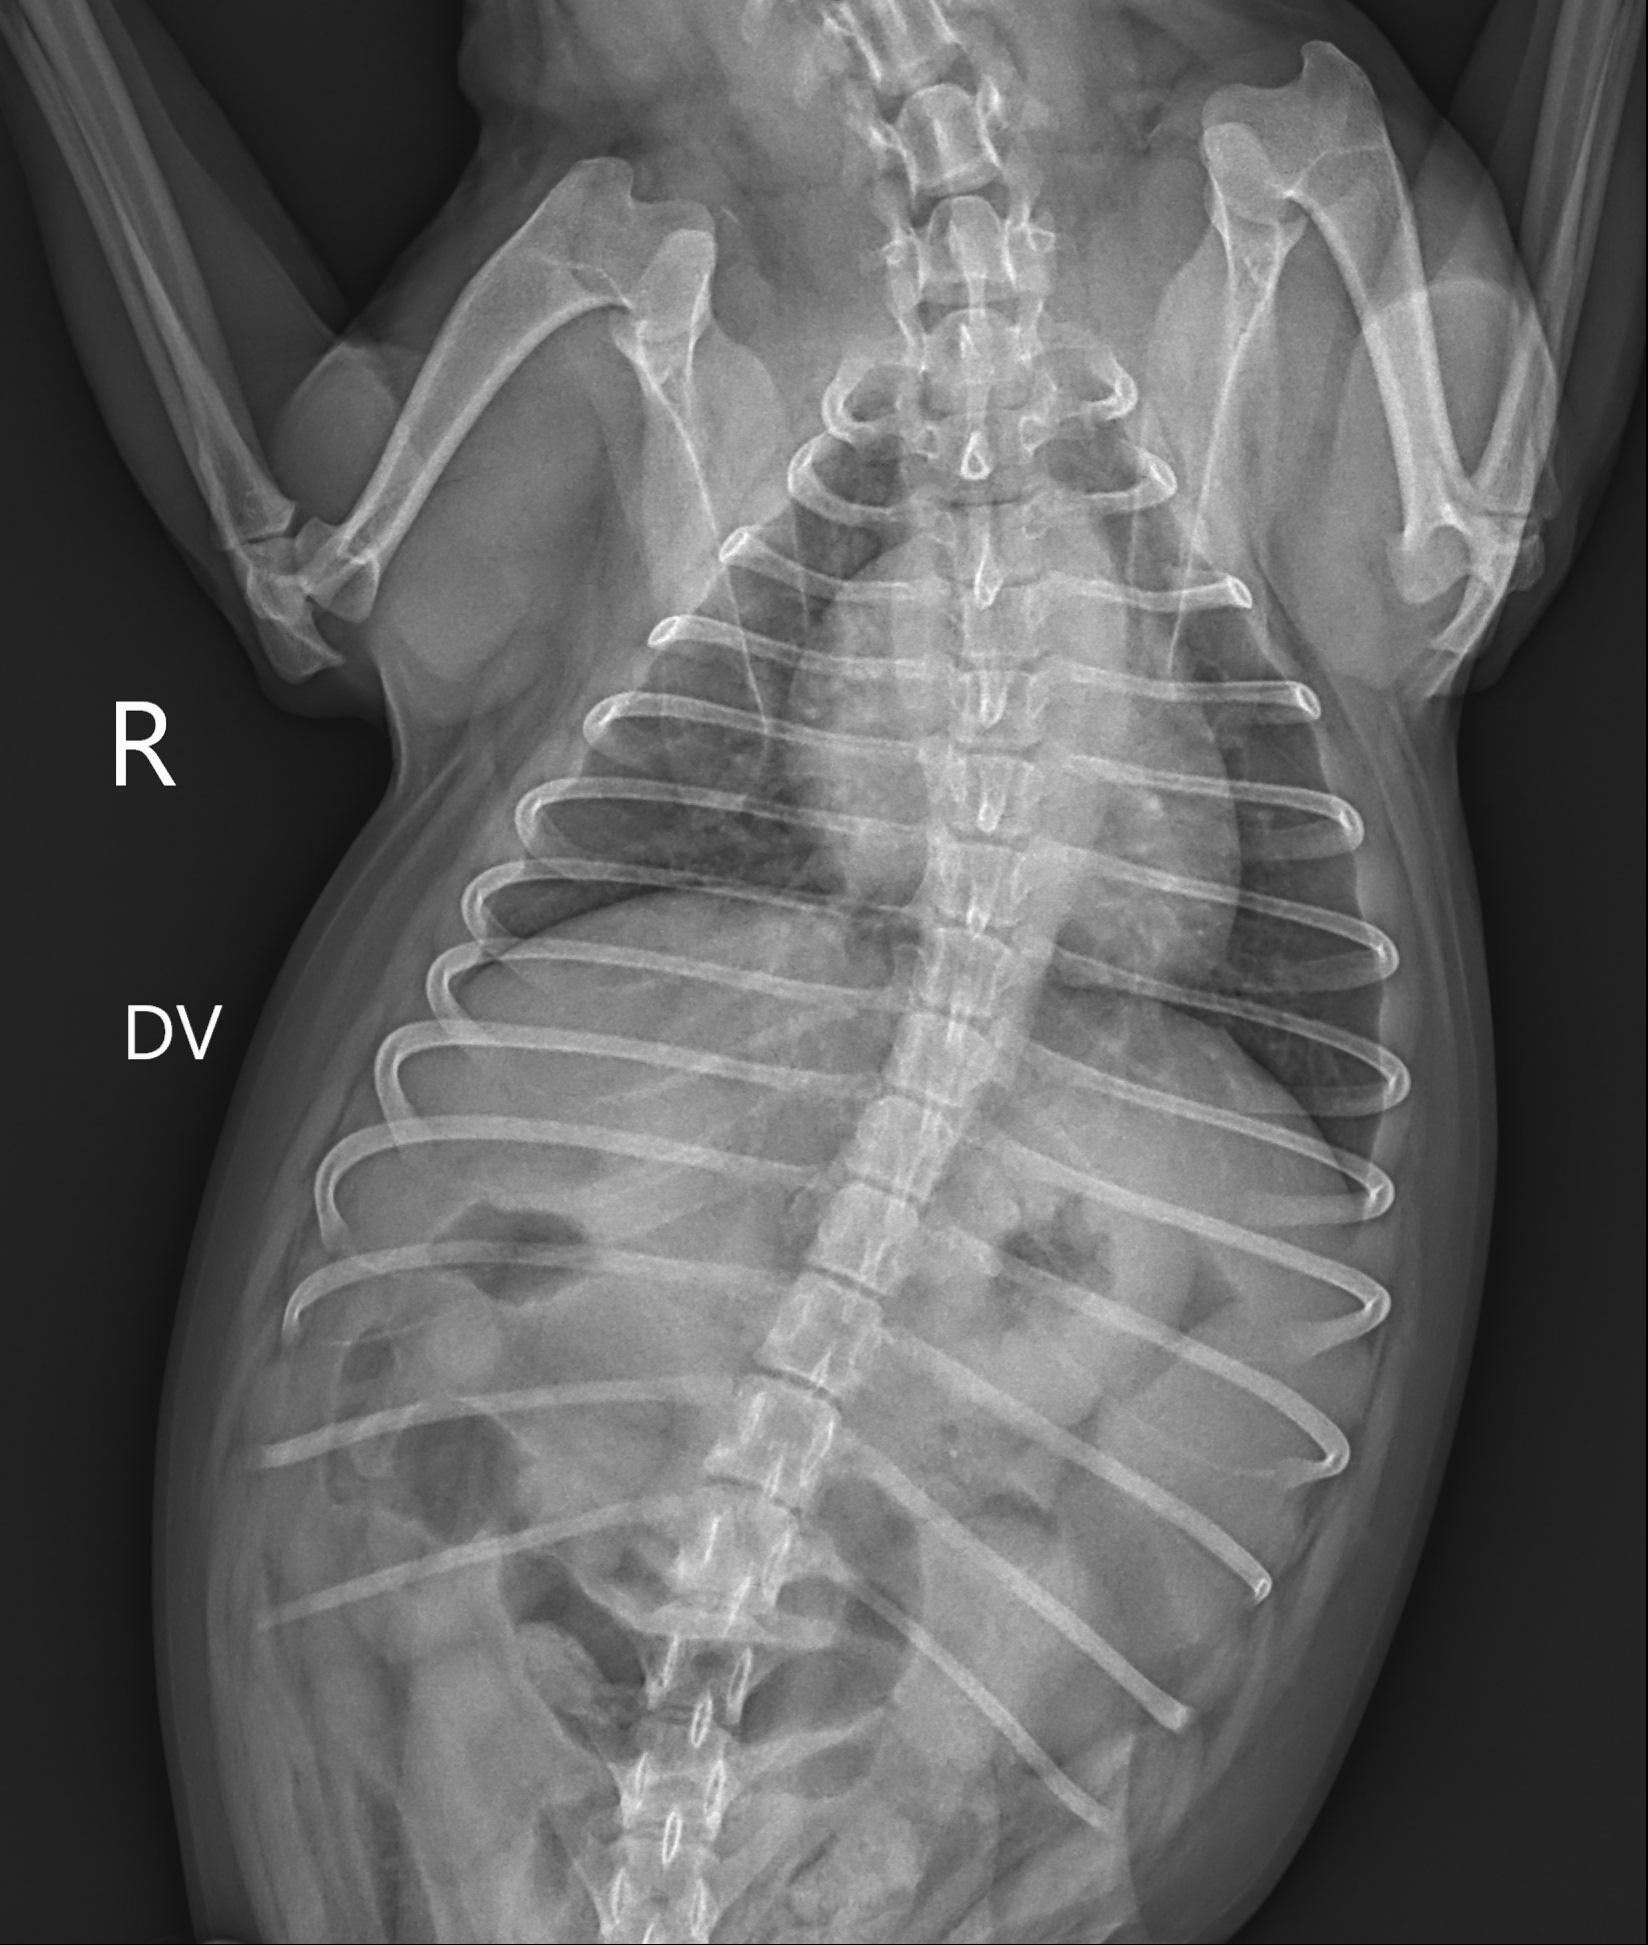

- ไอเสียงเหมือนห่าน ไอหนักช่วงตี 2-4

วินิจฉัย

- หลอดลมอักเสบ

- ไอ หายใจไม่ออก นอนไม่ได้ ลิ้นม่วง

วินิจฉัย

- น้ำท่วมปอด

- หลอดลมตีบ